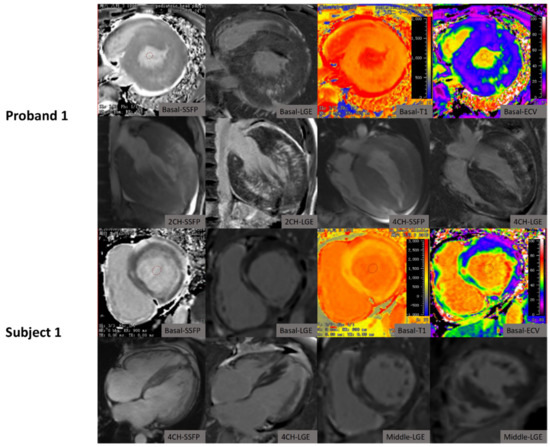

| Proband 1 | LAMP2 (c.64 + 1G > A) | 20 | M | 18.0 | Palpitation, DOE | II | Yes | NSR; ventricular preexcitation; NSST-T | 59.8 | 50.4 | 42 | 33.4 | Extensive fibrosis mainly in mid-myocardium of lateral wall with septal sparing | 1376.5 | 35.5 | ICD implantation; awaiting heart transplantation |

| Subject 1 | LAMP2 (c.64 + 1G > A) | 44 | F | 23.4 | DOE; edema | II | No | NSR; Short PR intervals; PVC | 16.9 | 27.8 | 16 | 18.9 | Non-ischemic sub-endocardial LGE mainly in lateral wall and transmural LGE pattern | 1581.2 | 43.9 | Heart failure managed; awaiting heart transplantation |